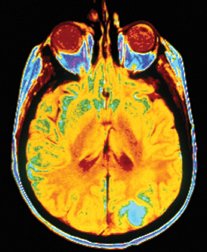

In this technology, called magnetic resonance imaging (MRI), a technician exposes a portion of a patient’s body to a strong magnetic field. Like compass needles swiveling north, protons in the tissue’s atoms align with the applied magnetic field. Then, the technician directs a radio pulse at the tissue, scrambling the positions of the protons. When the pulse ends, the protons revert to their original positions, emitting measurable radio signals.

It helps that water makes up two-thirds of the human body. Water is readily identifiable in MRI because the protons in each molecule’s two hydrogen atoms give off radio waves in a recognizable frequency. By detecting this signature and generating images from it, MRI allows a physician to distinguish between fluids and soft tissues such as brain and muscle, neither of which shows up clearly on X rays.

A typical MRI machine is roughly the size of an office cubicle and has a long tube through its middle. A patient lies in this tube, surrounded by the powerful magnet at the heart of the machine. MRI images can reveal injuries, cancer, brain damage, and other tissue abnormalities. The technology differs from X rays and computed tomography, technologies for which scientists won Nobel prizes in 1901 and 1979, respectively. While those devices use ionizing radiation to create images of internal tissues, MRI relies on apparently harmless radio waves and magnets.